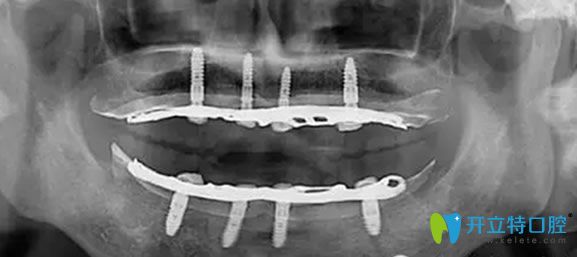

全口數(shù)字化X光影像

經(jīng)過一個月的漫長等待,老媽終于做了種植牙,當(dāng)場就拿蘋果做實驗,感覺種出來的牙齒和真牙一樣舒服。老媽再次擁有滿口舒適的好牙,恢復(fù)了咀嚼功能,真心覺得很不錯,感覺醫(yī)生技術(shù)水平也很專業(yè),很細心,走的時候還給我們囑咐種植牙的術(shù)后護理方法。